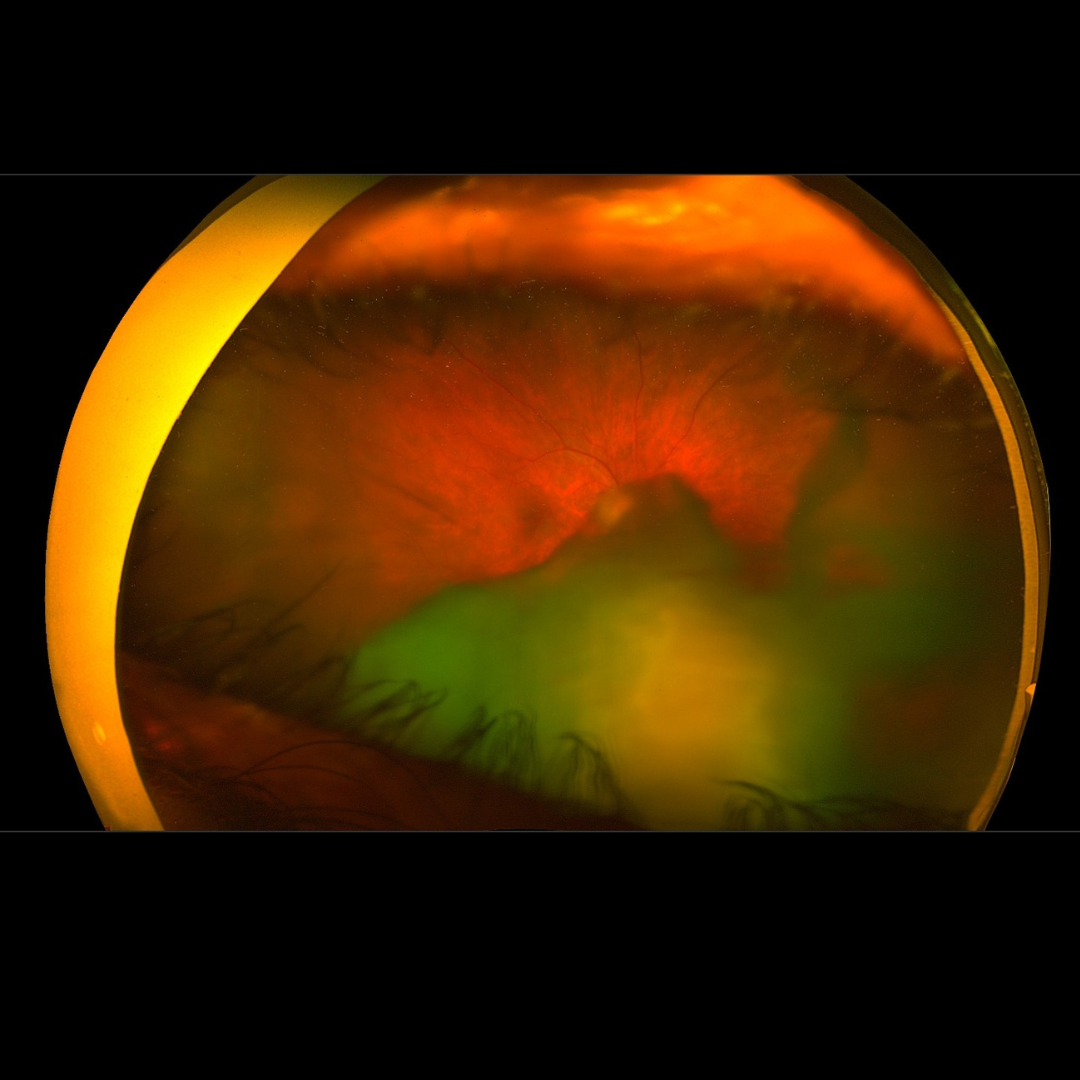

Complications of cataract surgery can include posterior capsule opacification (PCO), also called secondary cataract, which is the clouding of the lens capsule. Other potential complications include infection, inflammation, and retinal detachment. These complications can affect vision quality, but most are treatable with timely medical intervention.

Slit-lamp examination and optical coherence tomography (OCT) are used to identify and assess complications such as posterior capsule opacification or retinal detachment